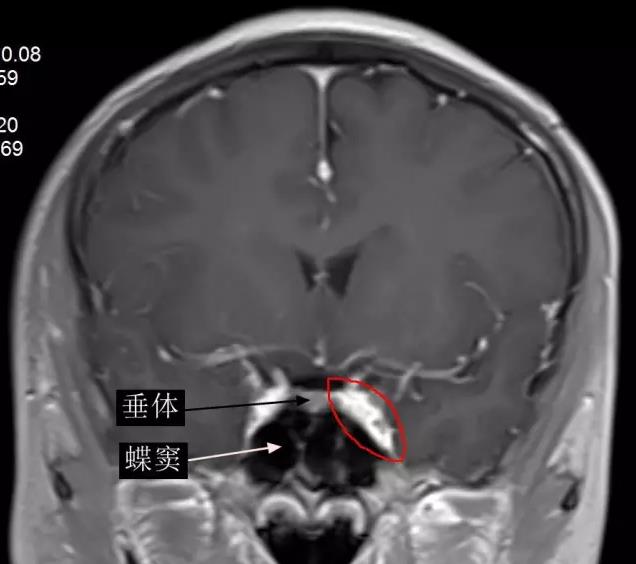

海綿竇位置影像冠狀位顯示 (增強磁共振圖像,下圖中紅圈內高信號區即左側海綿竇)